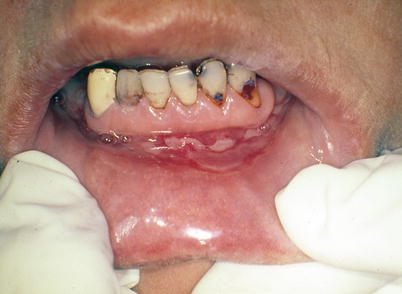

Fig. 2.33

Patient exhibiting a linear and irregular “snail track” erythematous lesion on the upper lip, which has been classically described by Alfred Fournier as one of the clinical signs of secondary syphilis. It should be observed that it is the patient lifting their own upper lip, as professionals must use gloves during physical examination to avoid possible contamination